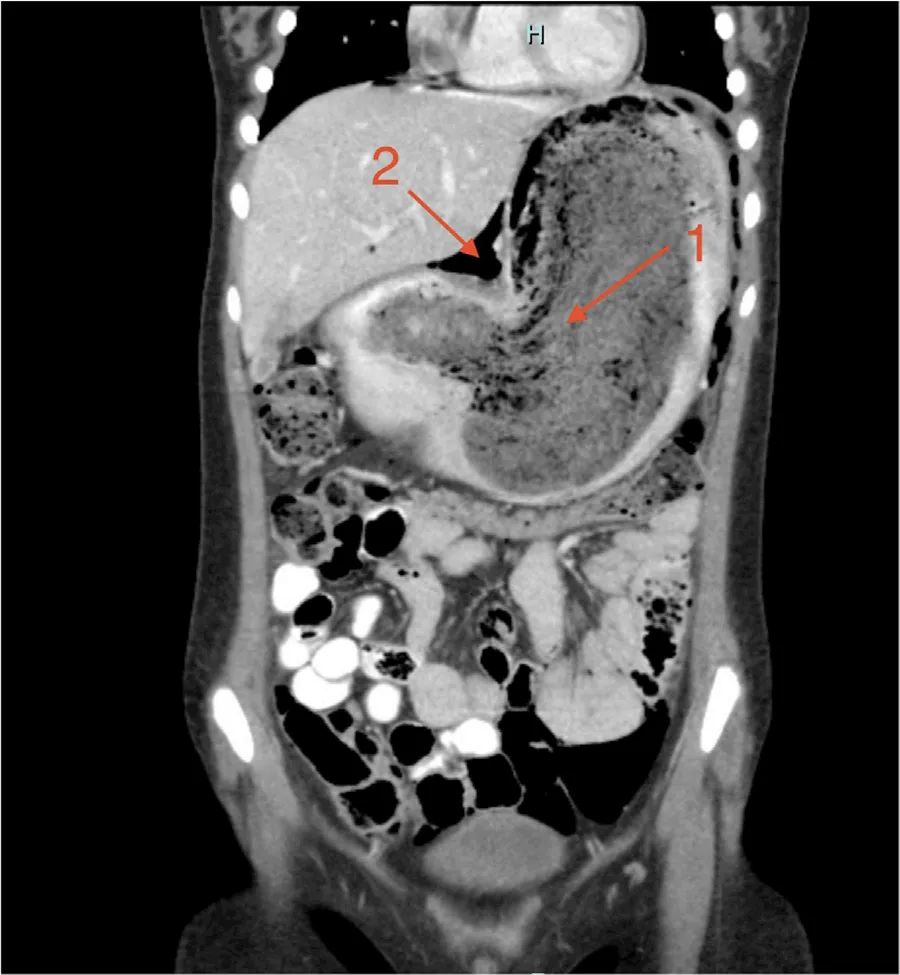

在过去一年中,患儿体重下降30磅,并出现进行性乏力和腹胀。入院时体温正常,生命体征符合其年龄特征。查体可见中线/上腹部存在明显肿块,实验室检查显示

图2